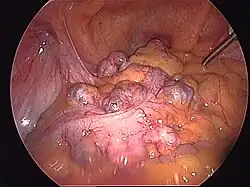

- Schematyczne obrazy jelita grubego i uchyłków esicy i śródoperacyjne obrazy uchyłków i nowotworu jelita grubego

Śródoperacyjny widok uchyłków esicy (operacja laparoskopowa).